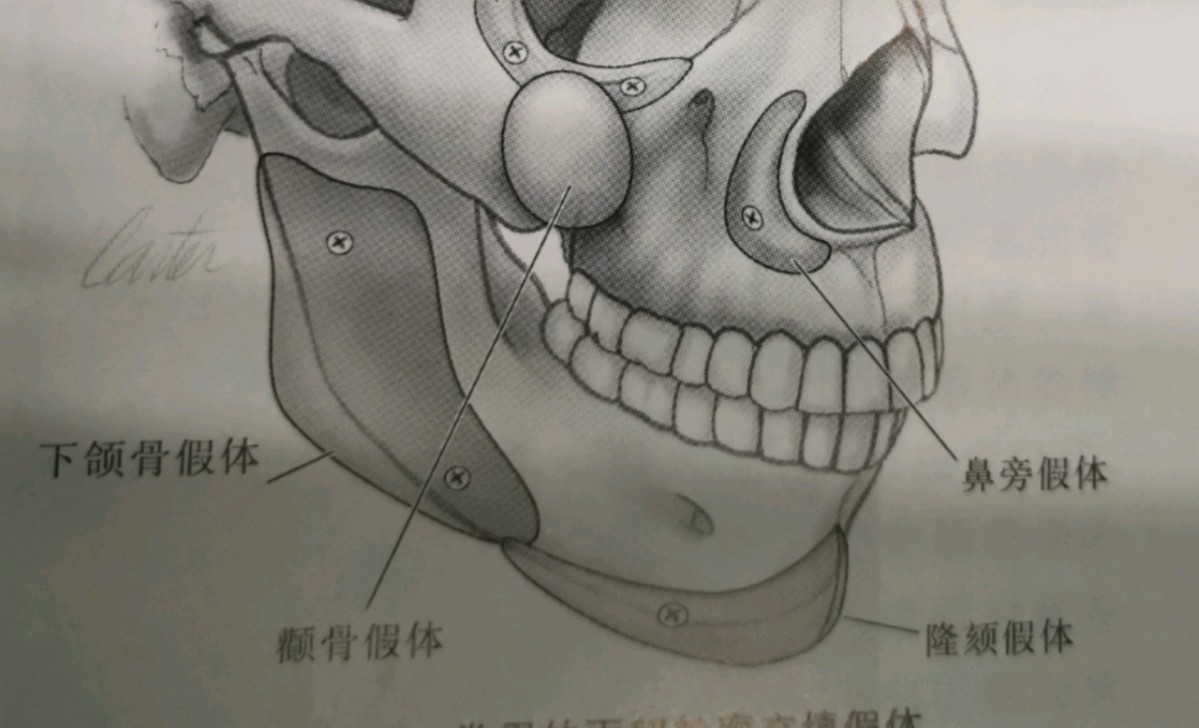

二、假体隆下颏

1、硅胶假体:

适应症:硅胶假体隆颏术比较适合咬合关系正常的轻度和中度小颏畸形(较严重的小颏畸形、咬合关系明显异常、下颌肥大、下唇肥厚等不合适),可使到下颏部适当的向下延长并起到选择性矫正下颌后缩畸形。

优点:硅胶假体材质运用广泛并且非常安全,排斥和感染情况非常少见,雕刻塑型,植入取出的把握难度较低,价格也相对亲民。

缺点:硅胶假体材质较硬,缓冲作用较低,在受压的情况下没有任何缓解过程,直接作用于骨质上,是引起骨吸收的一个潜在因素。并且由于不需要进行附加固定,远期会出现骨质压迫吸收和移位可能。硅胶有时候和下颌骨不贴合,使得下巴不够圆润。

2、膨体:

优点:膨体是目前公认生物相容性较好的假体植入材料,具有坚实,柔软几允许组织细胞和血管可长入其微孔,置入颏部后充填效果完美且与周围组织紧密镶嵌,形态和手感均自然逼真。

缺点:虽然膨体材料独特的微孔可以使其与周围组织紧密镶嵌,但正因为这种超微结构,易于细菌的隐藏和残留,一旦发生感染,就难以控制,所以膨体雕刻及手术全过程需要严格遵守无菌操作,口腔内本身就是一个有菌的环境,很难做到完全无菌操作,避免近远期感染的发生尤其重要。此外,膨体的取出相对硅胶假体而言较难,价格也相对较高。

3、Medpor(曼特泼)

优点:Medpor主要成分是聚乙烯(PE),为多孔、块状、质硬物体。目前国内安全运用比较广泛的高端假体材料,组织相容性好,无明显排斥反应,并且感染率低。假体有良好的韧性,精雕塑型效果较好。组织血管长入微孔,周围无明显纤维包裹挛缩。假体稳定性强,手术操作简单。

缺点:与周围组织紧密镶嵌,移除难度较硅胶假体而言大。作为高端假体材料,相对硅胶假体和膨体而言要贵。